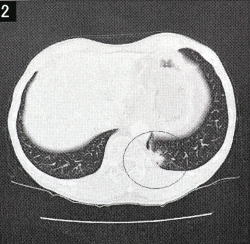

◆CT画像に写った放射線性肺臓炎(右の○の部分)。検査のたびごとに「X線診断レポート」を渡され、それには所見や画像が掲載されている。話だけではなく、こうしたデータを渡してもらえるのはありがたい。

所見にはこうあった。

〈肺野〉左S10にconsolidationが出現している。radiation pneumonitisと考える。転移を示唆する所見なし。

先生の説明では、肺に硬結・硬化が見られ、放射線性肺臓炎だと考えられる――ということだ。

今日は東病院で診察。7月1日に受けた検査の結果を聞く。南の島で元気を取り戻したと思ったが、放射線の晩期障害が出ていた。放射線性肺臓炎。CT画像には左の肺の先端に白い影が写っている。

この肺炎は、5〜7パーセントの確率で発生し、3パーセントは入院が必要になるという。わたしの場合、放射線を当てる範囲が広かったから、肺もけっこうやられたのだろう。ただ、それほどひどくはなく、しばらく様子をみることになった。咳、熱、息切れ、胸痛に要注意。